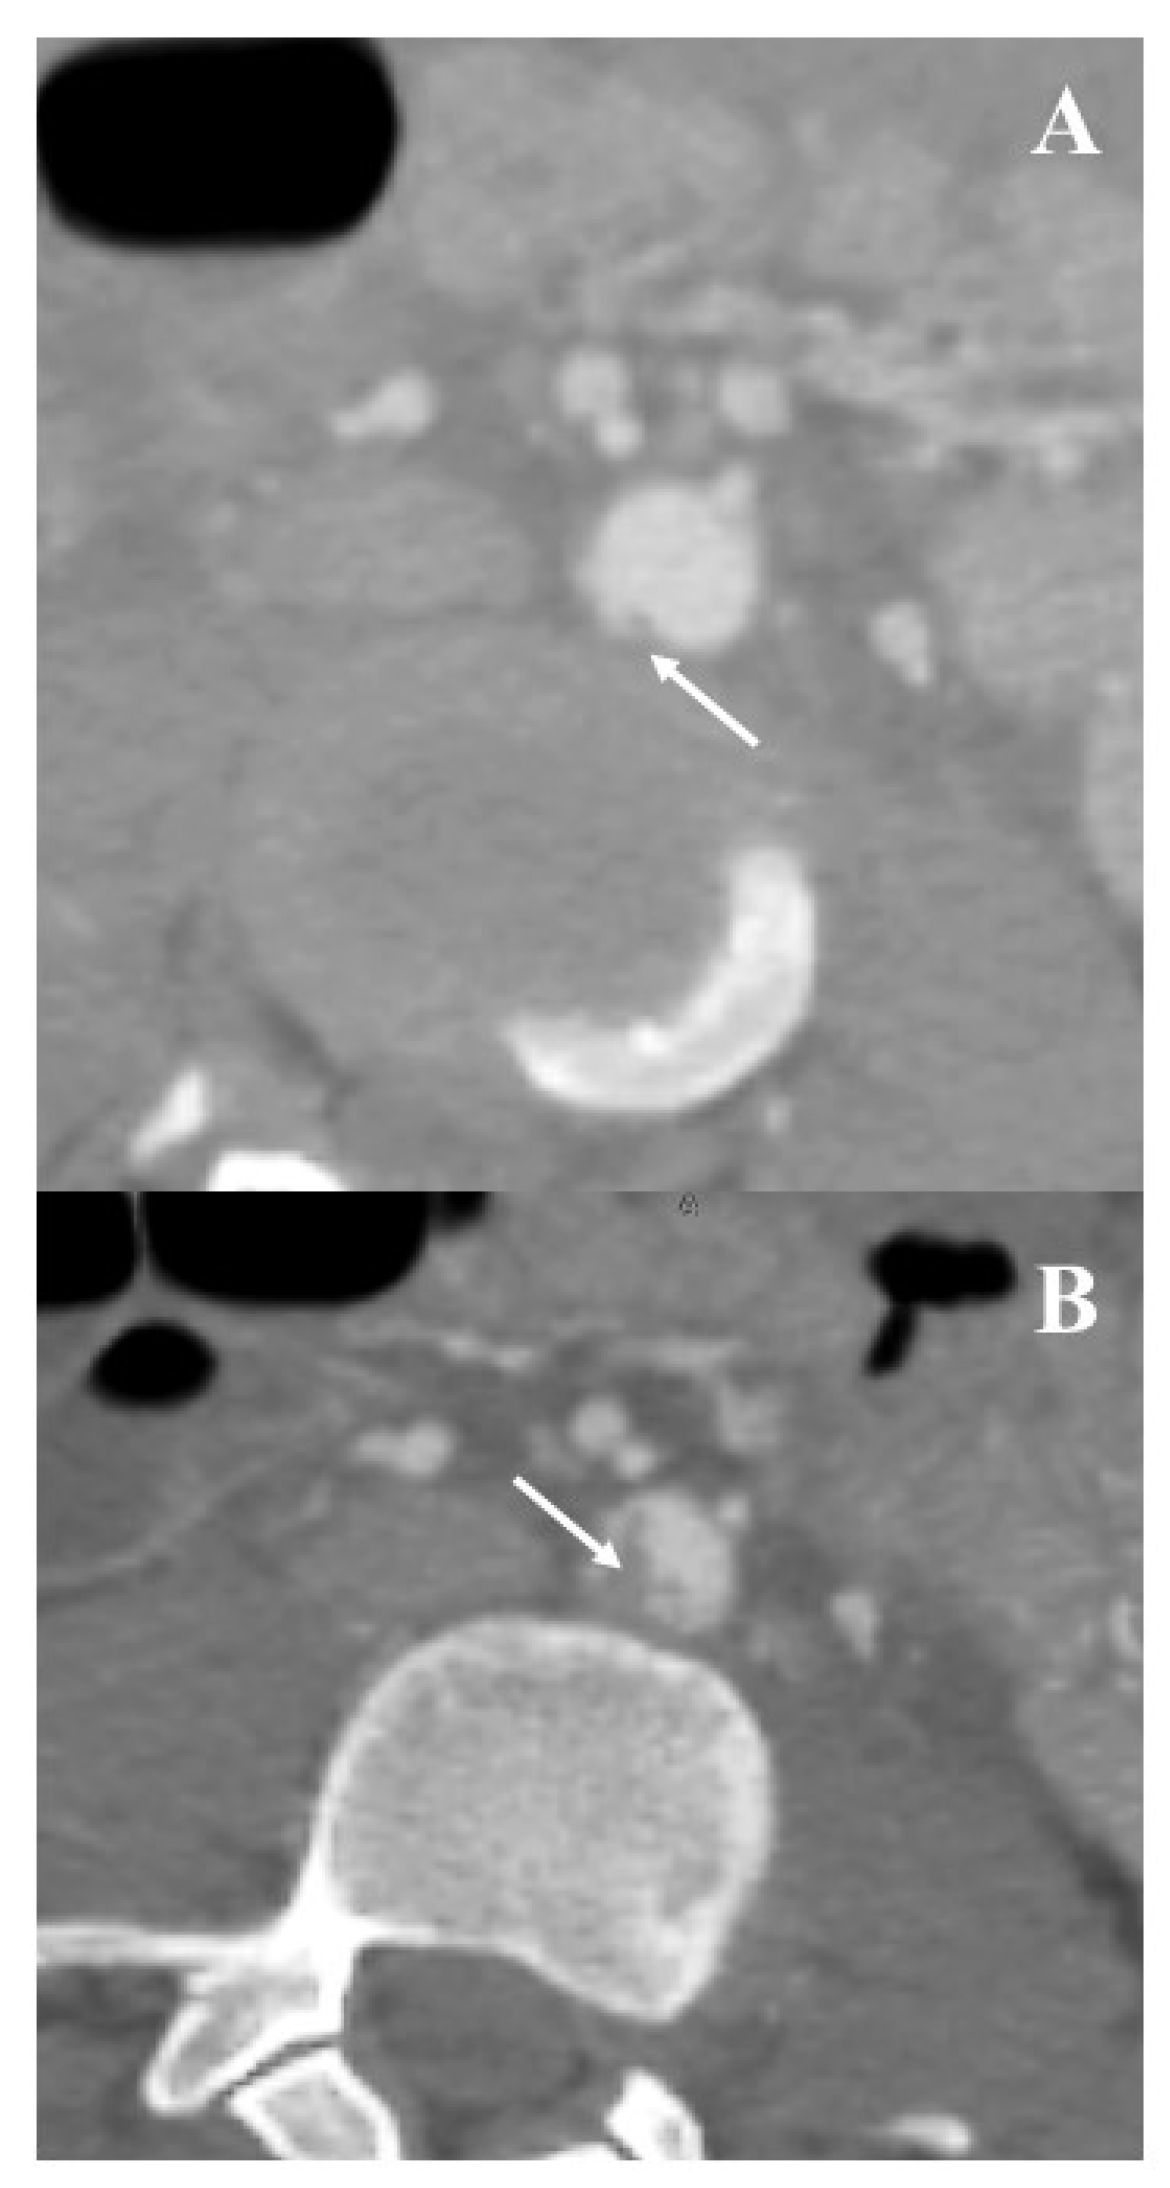

3.2. Institutional Case Report #2—Intra-Abdominal Injury and Endovascular Treatment